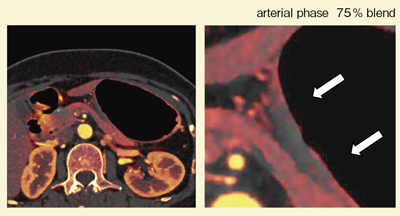

症例2は,体下部後壁小彎のUc型の早期胃がんで,病理診断結果は低分化腺癌であった。造影CTにて体下部後壁に浅い陥凹が認められ,動脈相でわずかに欠損が認められ,門脈相で濃染が回復し,平衡相で以前より良く濃染している様子が描出された。おそらく,生検やクリッピングにより,少し線維化が起こっているためと考えられるが,iodine imageを重ねると,50%ブレンドした画像(図6)では,四角で囲った部分では他の部分の粘膜が良く濃染しているにもかかわらず,粘膜の染まりはほとんど認められなかった。さらに,75%ブレンドした画像(図7)では,部分的な造影欠損が明瞭に認められ,低分化腺癌であることがCTで確実に診断できた。

![]() 図7 症例2:75%ブレンドiodine image |